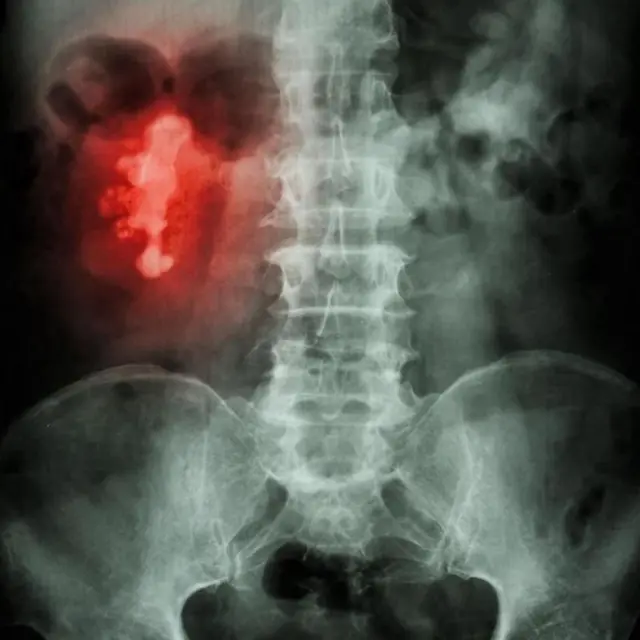

ਗੁਰਦੇ ਦੀ ਪੱਥਰੀ ਦਾ ਆਕਾਰ ਵੀ ਵੱਖਰਾ ਹੋ ਸਕਦਾ ਹੈ। ਇਹ ਚੌੜਾਈ ਵਿੱਚ ਇੱਕ ਮਿਲੀਮੀਟਰ ਤੋਂ ਘੱਟ ਚੌੜਾਈ ਤੋਂ ਲੈ ਕੇ ਇੱਕ ਸੈਂਟੀਮੀਟਰ ਜਾਂ ਉਸ ਤੋਂ ਵੱਧ ਤੱਕ ਹੋ ਸਕਦੇ ਹਨ।

ਪੱਥਰੀ ਅਸਾਧਾਰਨ ਸ਼ਕਲ ਦੀ ਵੀ ਹੋ ਸਕਦੀ ਹੈ। ਪਰ ਜੇ ਕਿਡਨੀ ਕੈਨਾਲ (ਕੈਲਿਸ) ਦੀਆਂ ਸ਼ਾਖਾਵਾਂ ਦੇ ਅੰਦਰ ਪੱਥਰੀ ਬਣਨਾ ਸ਼ੁਰੂ ਹੋ ਜਾਂਦੀ ਹੈ, ਤਾਂ ਇਹ ਹਿਰਨ ਦੇ ਸਿੰਗ ਦਾ ਆਕਾਰ ਵੀ ਲੈ ਸਕਦੀ ਹੈ। ਇਸ ਨੂੰ ਸਟੈਗਹੋਰਨ ਕੈਲਕੂਲਸ ਕਿਹਾ ਜਾਂਦਾ ਹੈ।